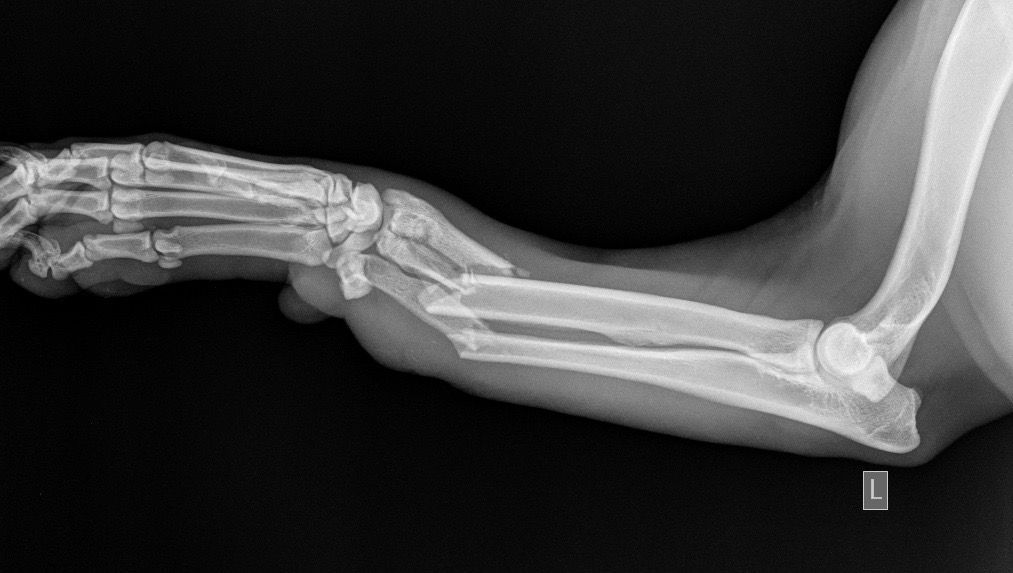

Η κα Μακρή δημοσίευσε σήμερα στο facebook την γνωμάτευση του κτηνιάτρου σχετικά με την εξέλιξη της υγείας του ζώου. Σε αυτή αναφέρεται ότι: «Ο σκύλος έφερε συντριπτικά ενδοαρθρικά κατάγματα με μετατόπιση στο κάτω τρίτο του αριστερού αντιβραχίου και στο κάτω τρίτο του αριστερού μηριαίου. Ολοκληρώθηκε με επιτυχία η πρώτη χειρουργική επέμβαση που αφορούσε την ανάταξη και οστεοσύνθεση του αριστερού αντιβραχίου. Λόγω της σοβαρότητας του κατάγματος η διάρκεια της χειρουργικής επέμβασης ήταν 4 ώρες και 25 λεπτά και ο σκύλος ανένηψε φυσιολογικά».